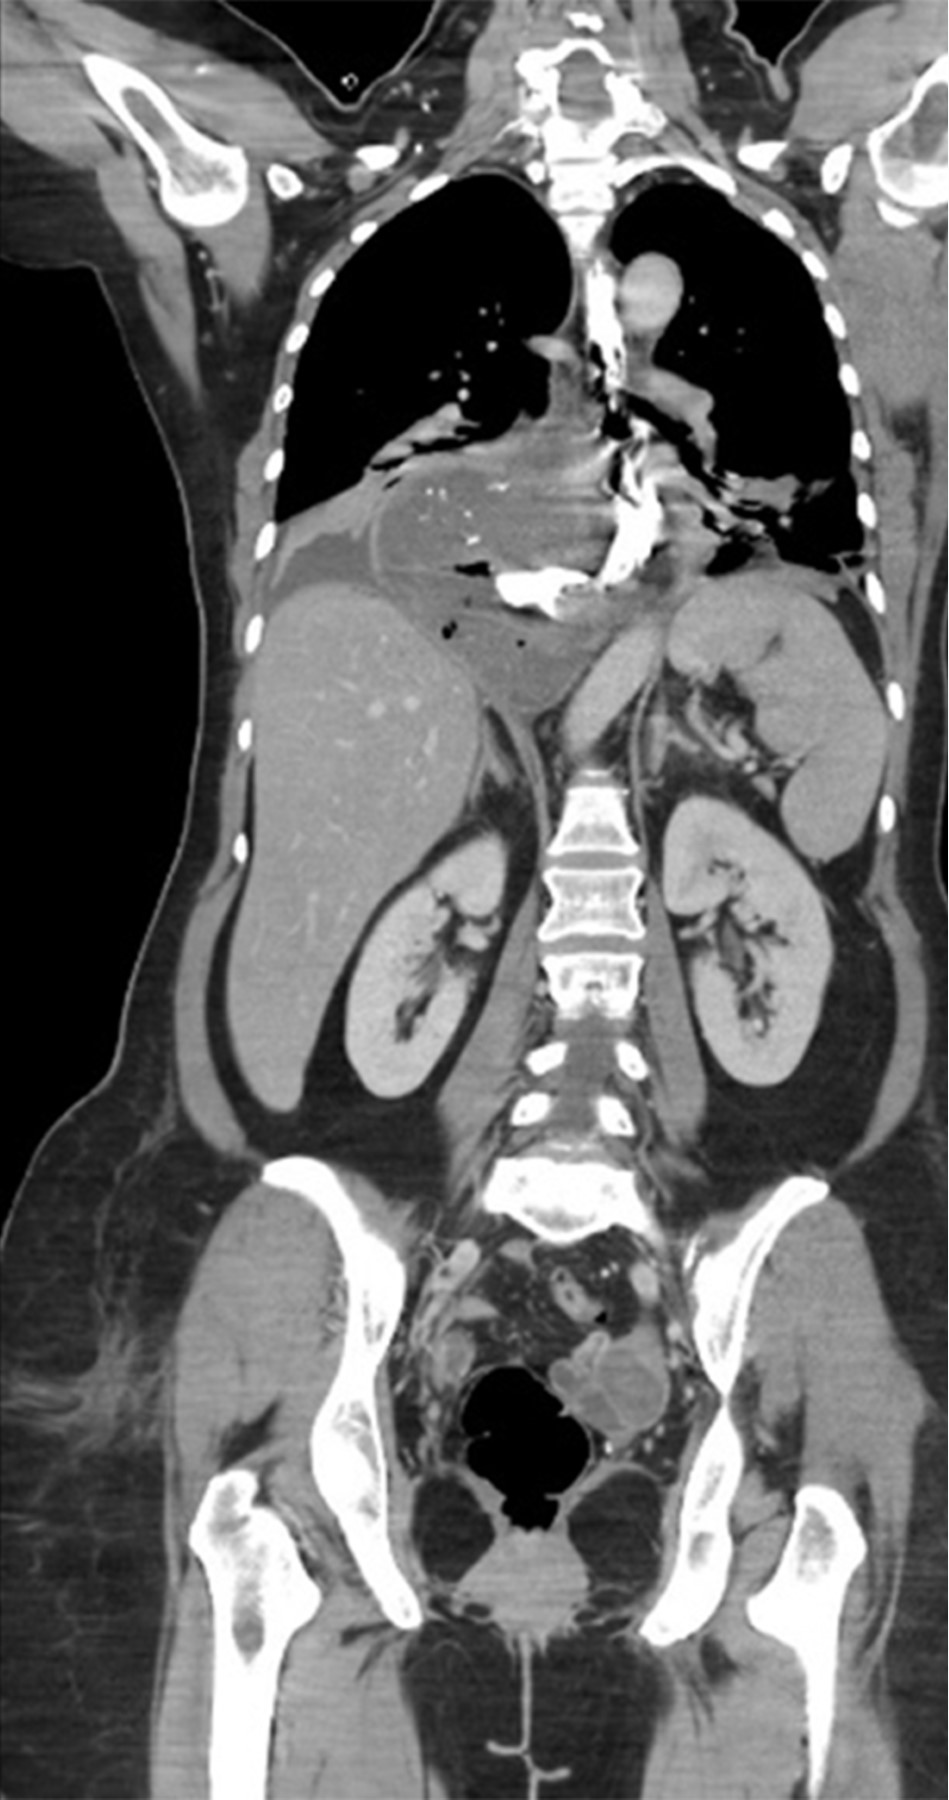

Mujer de 54 años con antecedente de hipertensión arterial sistémica de 16 años de evolución en tratamiento médico con losartán 50 mg cada 24 horas en buen control, antecedente de histerectomía total abdominal hace 14 años por miomatosis uterina, colecistectomía laparoscópica hace cuatro años por colecistitis crónica litiásica ambas sin complicaciones aparentes, inicia su padecimiento de 36 horas de evolución con dolor torácico importante, fiebre no cuantificada y ataque al estado general, por lo que acude a su valoración en nuestra unidad, al interrogatorio dirigido refiere un historial de cinco años de sintomatología caracterizada por disfagia a la ingesta de alimentos sólidos. En la exploración física se encuentra una paciente en malas condiciones que presenta taquicardia de 120 pulsaciones por minuto, hipotensión de 90/60 mmHg, frecuencia respiratoria de 23 respiraciones por minuto, temperatura de 36.5 oC, palidez de tegumentos generalizada, a la auscultación del tórax lado derecho con disminución de los ruidos respiratorios con matidez a la percusión e incremento de las vibraciones vocales, el abdomen es plano, blando depresible no presentando datos de irritación peritoneal. En la analítica de laboratorio destaca una hemoglobina de 16.6 g/dl, hematocrito de 49.68%, leucocitos de 18 cel/mm3, neutrófilos de 89%. Se realizó una tomografía toracoabdominal, la cual mostró un tumor dependiente del esófago distal asociado con líquido libre en tórax y salida de medio de contraste de la luz del esófago (Figuras 1 y 2). Por el cuadro clínico presentado de perforación esofágica y mediastinitis se decide someter a la paciente a tratamiento quirúrgico.

Los estudios de imagen tales como esofagograma con bario, tomografía computarizada con contraste vía oral, esofagoscopia y el ultrasonido endoscópico son considerados herramientas de gran utilidad diagnóstica en esta patología.17 En el presente caso, la tomografía toracoabdominal reveló un tumor de gran tamaño que se originaba en el tercio inferior del esófago, que tras la administración del medio de contraste por vía oral se demostró una perforación de este órgano, requiriendo la necesidad de intervención quirúrgica de urgencia.